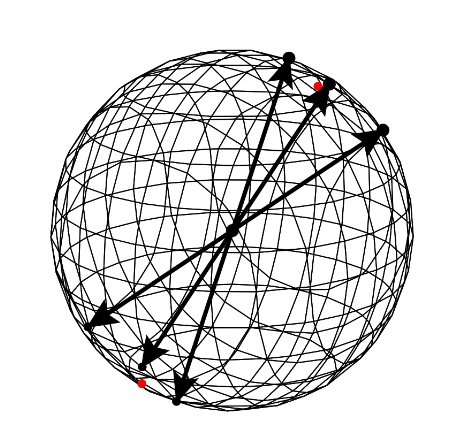

Due to practical constraints on the overall duration of dMRI measurements, the sampling of q-space is usually limited to one or several reference measurements with , as well as one or a few shells with constant , and thus constant . This is illustrated in Figure 1. Such setups focus on the directional dependence of the signal, and typically strive for a uniform distribution of gradient directions on these shells cheng2017single . Our codec assumes dMRI data with such a “shelled” structure, an assumption that is shared by well-established algorithms in the field Andersson2016a .

Traditional PDE-based image compression galic2008image ; 10.1007/978-3-030-56215-1_5 ; jumakulyyev2021lossless ; schmaltz2014understanding performs inpainting in image space, which relies on piecewise smoothness of the image. A key contribution of our current work is to additionally exploit the smoothness in q-space. As it can be seen in Figure 1, dMRI signals that are measured with similar gradient directions are correlated.

The general idea of q-space inpainting is illustrated in Figure 2: Once a certain number of diffusion-weighted images with different gradient directions are known, we can use them to predict images that correspond to a new direction. This happens at the voxel level, so that the prediction at a given location is entirely determined by values at the same location in the known images.

Given that our samples do not form a regular grid, we numerically solve these equations using Finite Element Methods (FEM) Chizhov:2021 ; logg2012automated . For this, we first construct a 3D Delaunay tessellation from the set of all gradient vectors and their antipodal counterparts , and then extract a triangular surface mesh from it. Figure 3 shows an example of the given vectors (left), and the resulting triangular mesh (right).